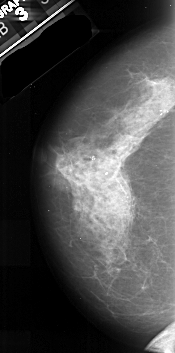

A_1035_1.LEFT_MLO

LEFT_MLO LINES 5491 PIXELS_PER_LINE 2596 BITS_PER_PIXEL 16 RESOLUTION 42 NON_OVERLAY